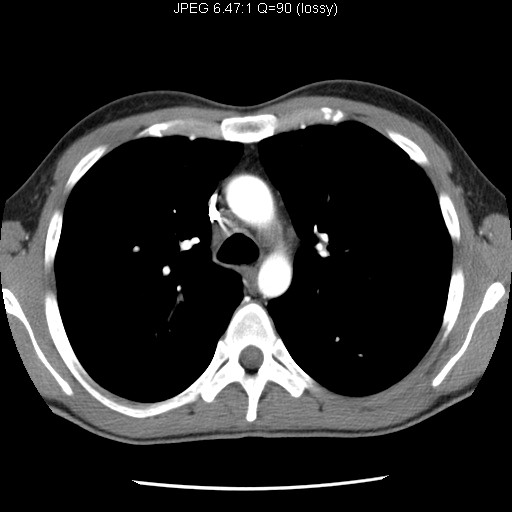

Identify the vascular structures. Click the image for labeling.